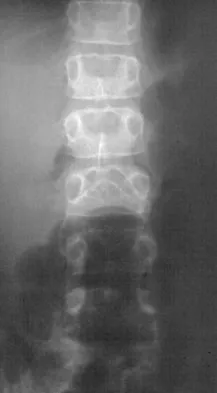

In patients with neurofibromatosis, what is the most important sign of impending rapid progression of a spinal deformity?

Explanation

Neurofibromatosis can progress very rapidly. Rib penciling is the only singular prognostic factor. Significant progression has been observed in 87% of the curves with three or more penciled ribs. The other factors are often present but do not have a high correlation with rapid, severe progression. Crawford AH, Schorry EK: Neurofibromatosis in children: The role of the orthopaedist. J Am Acad Orthop Surg 1999;7:217-230.

References:

- Durrani AA, Crawford AH, Chouhdry SN, Saifuddin A, Morley TR: Modulation of spinal deformities in patients with neurofibromatosis type 1. Spine 2000;25:69-75.